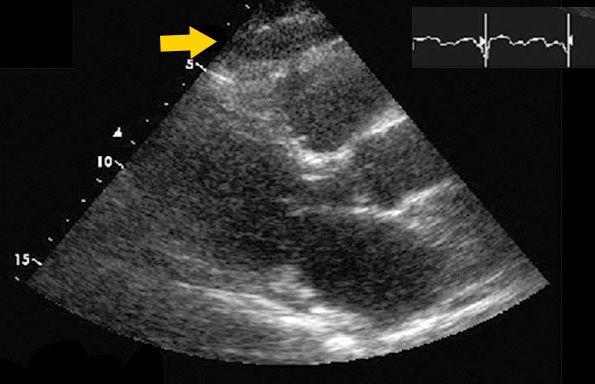

超声心动图胸骨旁长轴位显示右心室游离壁的外膜脂肪(箭头所示)。